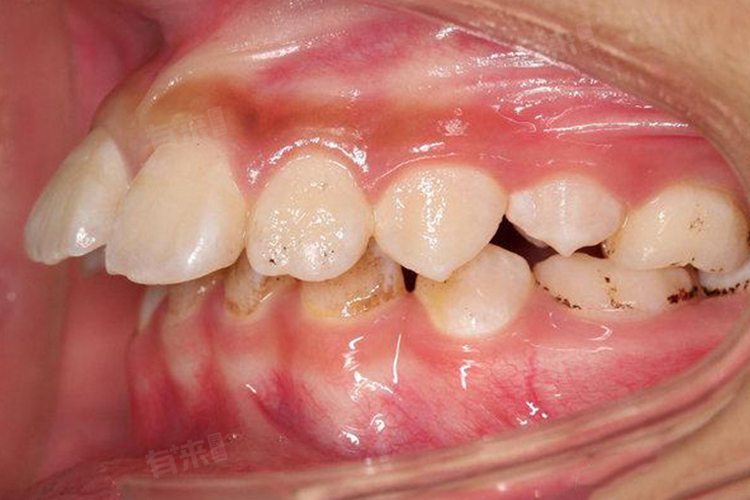

天包地即上颌牙齿覆盖下颌牙齿过多,属于牙颌面畸形,不仅影响美观,还可能影响口腔功能和颞下颌关节健康,可以通过传统金属托槽矫正、陶瓷自锁托槽矫正等方法矫正。